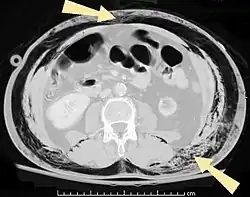

| An abdominal CT scan of a patient with subcutaneous emphysema (arrows) | |

Significant cases of subcutaneous emphysema are easy to diagnose because of the characteristic signs of the condition.[1] In some cases, the signs are subtle, making diagnosis more difficult.[13] Medical imaging is used to diagnose the condition or confirm a diagnosis made using clinical signs. On a chest radiograph, subcutaneous emphysema may be seen as radiolucent striations in the pattern expected from the pectoralis major muscle group. Air in the subcutaneous tissues may interfere with radiography of the chest, potentially obscuring serious conditions such as pneumothorax.[18] It can also reduce the effectiveness of chest ultrasound.[28] On the other hand, since subcutaneous emphysema may become apparent in chest X-rays before a pneumothorax does, its presence may be used to infer that of the latter injury.[13] Subcutaneous emphysema can also be seen in CT scans, with the air pockets appearing as dark areas. CT scanning is so sensitive that it commonly makes it possible to find the exact spot from which air is entering the soft tissues.[13] In 1944, M.T. Macklin and C.C. Macklin published further insights into the pathophysiology of spontaneous Macklin's Syndrome occurring as a result of a severe asthmatic attack.